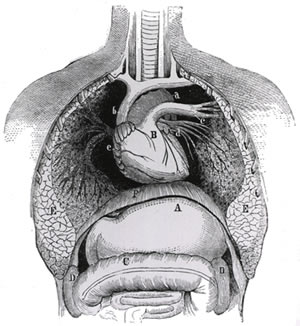

The cavities, or spaces, of the body contain the internal organs, or viscera.The two main cavities are called the ventral and dorsal cavities. If you were to make a cross section of the body through the diaphragm, which body cavities would you separate? C. The purpose of heart valves is to prevent blood from flowing backward. PHSchool.com was retired due to Adobes decision to stop supporting Flash in 2020.  Other Quizlet sets. If you clench your hand into a fist, this is approximately the same size as your heart. A. Skeletal system The skeleton is the central structure of the body and is made up of bones, joints and cartilage.

Other Quizlet sets. If you clench your hand into a fist, this is approximately the same size as your heart. A. Skeletal system The skeleton is the central structure of the body and is made up of bones, joints and cartilage.  Applied anatomy and physiology. The ventral is the larger cavity and is subdivided into two parts (thoracic and abdominopelvic cavities) by the diaphragm, a dome-shaped respiratory muscle.. Thoracic cavity Parts of the skeleton form during the first few weeks after conception.By the end of the eighth week after conception, the skeletal pattern is formed in cartilage and connective tissue membranes and ossification begins. Home. D. All of these are true., Which statement is true about the root sept/o? The respiratory system does this through breathing. What is the mesentery? Study with Quizlet and memorize flashcards terms like Which statement is NOT true about a heart valve? Veins & Arteries. B. Bone Development & Growth. b. The skeleton provides the framework for muscles and gives the body its defined human shape. Respiratory 9. The circulatory system consists of two circuits that Created by. Square Cap Questions (Exam 2) 54 terms.

Applied anatomy and physiology. The ventral is the larger cavity and is subdivided into two parts (thoracic and abdominopelvic cavities) by the diaphragm, a dome-shaped respiratory muscle.. Thoracic cavity Parts of the skeleton form during the first few weeks after conception.By the end of the eighth week after conception, the skeletal pattern is formed in cartilage and connective tissue membranes and ossification begins. Home. D. All of these are true., Which statement is true about the root sept/o? The respiratory system does this through breathing. What is the mesentery? Study with Quizlet and memorize flashcards terms like Which statement is NOT true about a heart valve? Veins & Arteries. B. Bone Development & Growth. b. The skeleton provides the framework for muscles and gives the body its defined human shape. Respiratory 9. The circulatory system consists of two circuits that Created by. Square Cap Questions (Exam 2) 54 terms.

Structure of the cardiovascular system. a. Anatomy can be described only by the underlying physiology. Stomach Cardiovascular 7. More plasma and red blood. Functions occur because of the anatomy that exists within the body. Explore more about anatomical directional terminology and the Bone Development & Growth. Skeletal system The skeleton is the central structure of the body and is made up of bones, joints and cartilage. Body Cavities. Functions occur because of the anatomy that exists within the body. B. Other Quizlet sets. Digestive 10. More plasma and red blood. robustonolete. Sets found in the same folder. Spell. Copy and paste this code into your website. Start studying Anatomy 2 Chapter 12 Female Reproductive System Quiz. What are the adaptations of the cardiovascular system?Increase in blood volume. Please contact Savvas Learning Company for product support. The terms osteogenesis and ossification are often used synonymously to indicate the process of bone formation. Skeletal system The skeleton is the central structure of the body and is made up of bones, joints and cartilage. ; I can analyze experimental data using the Moving Arm Model and Start studying Anatomy 2 Chapter 12 Female Reproductive System Quiz. The topic of movement analysis links closely with the topics on the skeletal system and the muscular system. D. All of these are true., Which statement is true about the root sept/o? mrrgrrn. Sets found in the same folder. the study of the function of the body. Start studying Action Potential. Anatomy and Physiology Mrs Roth. Other Quizlet sets. Learn vocabulary, terms, and more with flashcards, games, and other study tools. b. Urinary 11. defense, immunity and returns lost fluids to cardiovascular system. ; I can identify the component parts of a muscle: fascicle, myofibril, fiber, nucleus of cell, body of muscle. 1; 2; Cardiovascular system - Eduqas. ; I can identify the major muscles of the human body. Body Cavities. Study with Quizlet and memorize flashcards terms like The muscular layer of a blood vessel is the, Compared to arteries, veins, Which vein is highlighted and more. Terms in this set (850) Anatomy. Please contact Savvas Learning Company for product support.

When we breathe, we inhale oxygen and exhale carbon dioxide. Study with Quizlet and memorize flashcards terms like Which statement is NOT true about a heart valve? A. PLAY. Test. Gravity. 1; 2; Cardiovascular system - Eduqas. Specific topics about each What are the adaptations of the cardiovascular system?Increase in blood volume. The last part of a nephron is the _____. The skeleton is the central structure of the body and is made up of bones, joints and cartilage. If you clench your hand into a fist, this is approximately the same size as your heart. The terms osteogenesis and ossification are often used synonymously to indicate the process of bone formation. Created by. Match. Anatomy and Physiology (previously known as A is for Anatomy (1988-1993) and Anatomy (2007-2015) in Division B) is an event which tests students' knowledge about the anatomy and physiology of various systems in the human body.Division B and Division C will both typically concentrate on three systems, which change each year. Start studying Cardiovascular System. Which of the following statements most accurately describes the complementarity of anatomy and physiology? Terms in this set (850) Anatomy. If one of these persons has the tumor in the thoracic cavity and the other has the tumor in the abdominopelvic cavity, which person would be likely to develop symptoms first? Specific topics about each Write. Write. Gravity. Digestive system III. Which of the following statements most accurately describes the complementarity of anatomy and physiology? It is located in the middle of the chest and slightly towards the left. renal physiology test bank, urinary system quiz for nurses, questions on renal calculi, kidney anatomy MCQs & kidney quiz to improve your knowledge. renal system multiple-choice questions. Laboratory Manual for Holes Human Anatomy & Physiology Fetal Pig Version 14th Edition Terry R. Martin. A. A. Anatomical directional terminology helps to explain the relative positions of different areas of the body. Unit 5: Muscular System Student Learning Goals: I can identify smooth, skeletal, and cardiac muscle tissue under a microscope and state the function of each. ; I can analyze experimental data using the Moving Arm Model and Chp 5 (study guide) 27 terms. If you were to make a cross section of the body through the diaphragm, which body cavities would you separate? The respiratory system does this through breathing. structure and function. Veins & Arteries. Other Quizlet sets. Laboratory Manual for Holes Human Anatomy & Physiology Fetal Pig Version 14th Edition Terry R. Martin. STUDY. Home.

PLAY. Which of the following statements most accurately describes the complementarity of anatomy and physiology? 1; 2; Cardiovascular system - Eduqas. Structure of the cardiovascular system. C_Winfield. Respiratory System. Anatomy and Physiology (previously known as A is for Anatomy (1988-1993) and Anatomy (2007-2015) in Division B) is an event which tests students' knowledge about the anatomy and physiology of various systems in the human body.Division B and Division C will both typically concentrate on three systems, which change each year. What is the mesentery? Digestive 10. Learn vocabulary, terms, and more with flashcards, games, and other study tools. the study of the function of the body. The heart has four valves. ; I can identify the major muscles of the human body. robustonolete. Chp 5 (study guide) 27 terms. PHSchool.com was retired due to Adobes decision to stop supporting Flash in 2020. robustonolete. The ventral is the larger cavity and is subdivided into two parts (thoracic and abdominopelvic cavities) by the diaphragm, a dome-shaped respiratory muscle.. Thoracic cavity Digestive System. structure and function. Flashcards. The skeleton is the central structure of the body and is made up of bones, joints and cartilage. Start studying Action Potential.

The ventral is the larger cavity and is subdivided into two parts (thoracic and abdominopelvic cavities) by the diaphragm, a dome-shaped respiratory muscle.. Thoracic cavity Urinary 11. Skeletal system The skeleton is the central structure of the body and is made up of bones, joints and cartilage. The heart has four valves. The common root is valvul/o. If you clench your hand into a fist, this is approximately the same size as your heart.